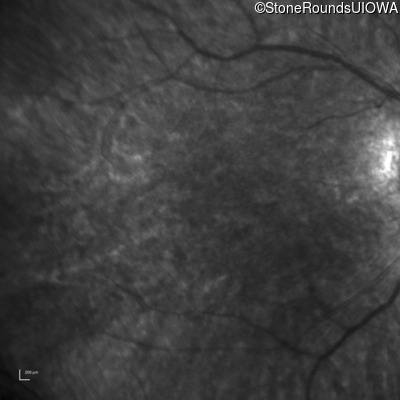

Infrared Fundus Photograph - Left - 20/80

Exemplar